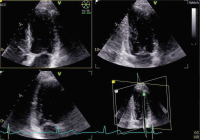

Echo

Abbildung 2: Triplane Aufnahme des linken Ventrikels mit einem 3D-Schallkopf (apikaler 4-Kammer-Blick links oben, 2-Kammer-Blick rechts oben, 3-Kammer-Blick links unten).